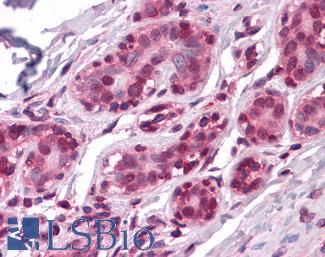

Estrogen Receptor / ESR1

Anti-ER Alpha / Estrogen Receptor antibody IHC staining of human breast. Immunohistochemistry of formalin-fixed, paraffin-embedded tissue after heat-induced antigen retrieval. Antibody LS-B10527 dilution 1:100.